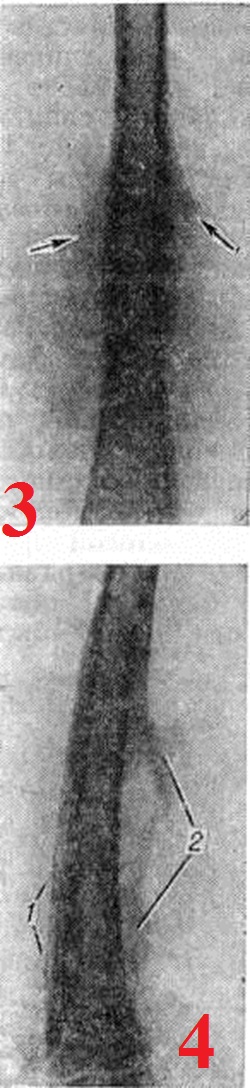

Рентгенодиагностика. Рентгенологические исследование выявляет локализацию, распространённость, форму, размеры, характер структуры, очертания периостальных наслоений, их взаимоотношения с корковым слоем кости и окружающими тканями. Рентгенологически различают линейные, бахромчатые, гребневидные, кружевные, слоистые, игольчатые и другого вида периостальные наслоения. Хронические, медленно текущие процессы в кости, особенно воспалительные, обычно вызывают более массивные напластования, как правило, сливающиеся с основной костью, что ведёт к утолщению кортикального слоя и увеличению объёма кости (рисунок 1). Быстро протекающие процессы ведут к отслоению надкостницы гноем, распространяющимся между ней и кортикальным слоем, воспалительным или опухолевым инфильтратом. Это можно наблюдать при остром остеомиелите, опухоли Юинга (смотри полный свод знаний Юинга опухоль), ретикулосаркоме (смотри полный свод знаний). Видимая в этих случаях на рентгенограмме линейная полоска новой кости, образованная надкостницей, оказывается отделённой от кортикального слоя полосой просветления (рисунок 2). При неравномерном развитии процесса таких полосок новой кости может быть несколько, в результате чего образуется картина так называемый слоистых («луковичных») периостальных напластований (рисунок 3). Гладкие, ровные периостальные наслоения сопровождают поперечную патологическую функциональный перестройку. При остром воспалительном процессе, когда под периостом скапливается гной под большим давлением, надкостница может разрываться, и на участках разрывов продолжает продуцироваться кость, давая на рентгенограмме картину неровной, «рваной» бахромы (рисунок 4).